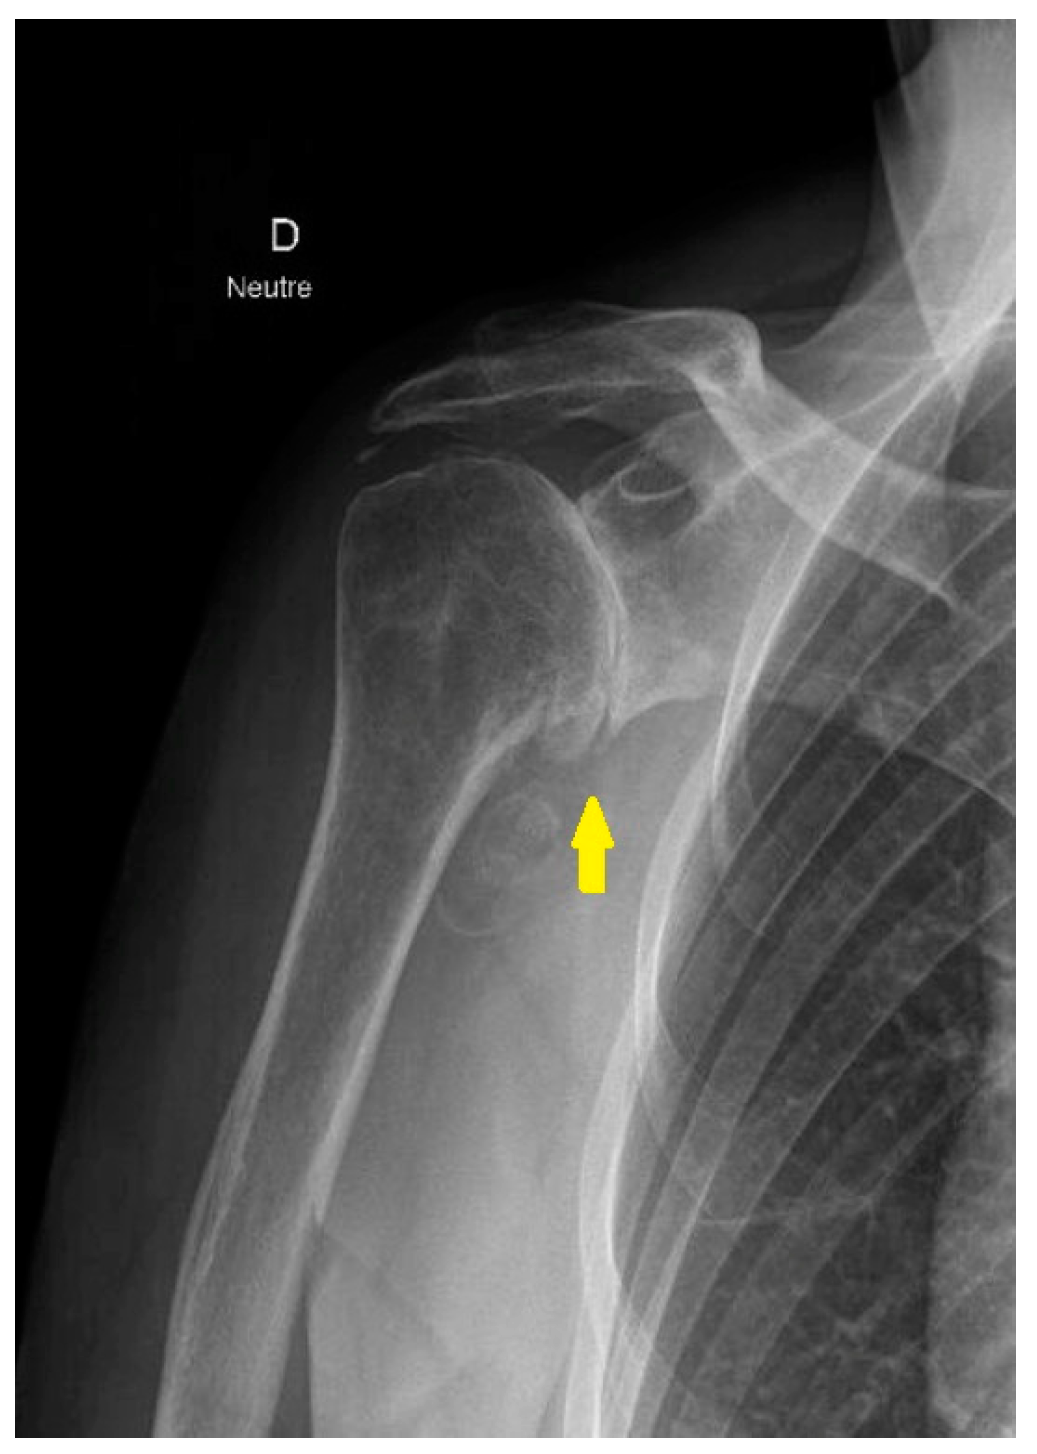

3.2. Proximal Humerus Fractures